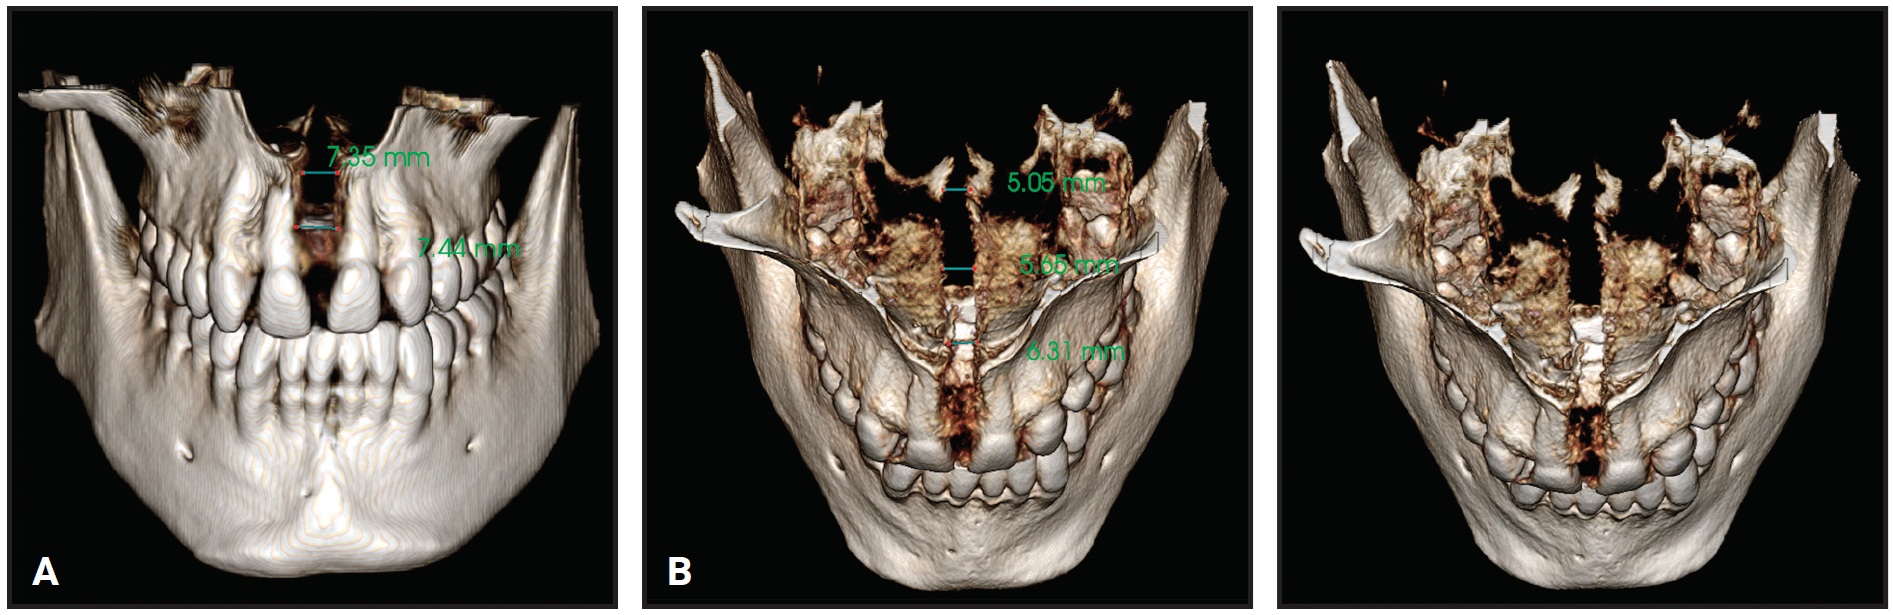

After 10 days with the second TSE, the transverse constriction and lateral crossbite had been corrected by pure skeletal expansion of the midpalatal suture (Fig. 6).

The amount of expansion ranged from 7.44mm in the anterior region to 5.05mm in the posterior region (Fig. 7).

Fig. 7 Case 1. A. Anterior expansion of midpalatal suture. B. Posterior expansion.

An increased open bite was observed due to premature contact between the upper and lower third molars (Fig. 8), but no buccal tipping or molar protraction occurred (Fig. 9).

At this point, the bilateral crossbite was still present. A new impression of the upper arch was used to simulate surgical forward movement of the maxilla into a Class I canine relationship (Fig. 15). Because this diagnostic simulation showed that the transverse expansion was adequate (Fig. 16), we decided to block the TSE and proceed with surgical-orthodontic treatment. The amount of expansion ranged from 6.1mm in the anterior region to 5.71mm in the posterior region (Fig. 17). No dental or periodontal side effects were observed, nor was any buccal tipping or molar protraction (Fig. 18).

Fig. 17 Case 2. Expansion of midpalatal suture.